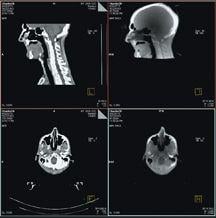

MVision, from Siemens Medical Solutions, is a volumetric in-line target imaging solution and the natural next step in Image-Guided Radiation Therapy (IGRT). Designed to work with Siemens’ linear accelerators, the system is the first commercial implementation of cone-beam technology utilizing a standard radiotherapy treatment beam. MVision makes it possible for the megavoltage (MV) source used for treatment to also create a 3-D image of the patient, enabling clinicians to “see inside” the patient at the most appropriate moment.

MVision fully integrates and automates all processes, including acquisition, reconstruction, registration, assessment, patient positioning and clinical review. With a few steps, therapists can calculate 3-D offsets, send them to the treatment couch to compensate for daily variations and safely deliver therapy.

The solution does not require an independent imaging source for IGRT, thus maximizing clinical accessibility and patient comfort. This innovation also frees caregivers from performing unnecessary electromechanical maintenance, so they can focus on patient care.